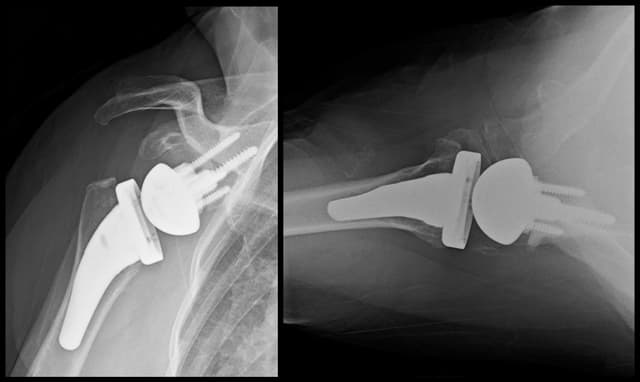

Post-op